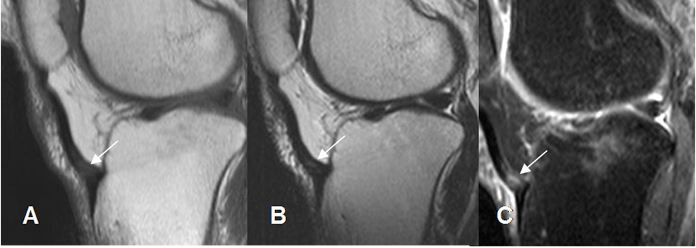

Fig 149 A. Tendinitis aguda del patelar.

A: RM sagital en T1, B: RM sagital en T2 y C: RM sagital en STIR. Inserción del tendón patelar hipointenso en T1 e hiperintenso en T2 y STIR, por inflamación aguda.